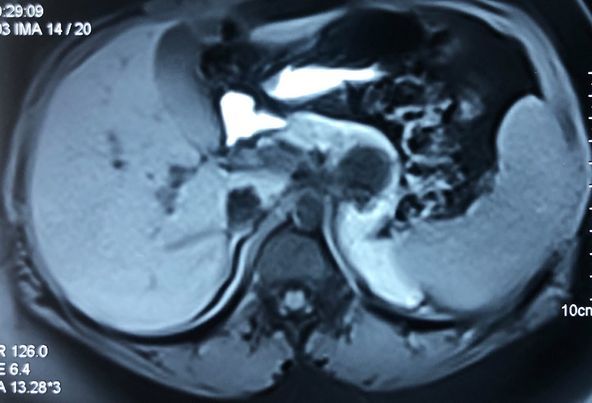

With chemotherapy improved survival with quality of life for Stage 4 cancer patient

Interesting Images March 2019 : Patient came with an early stage carcinoma rectum, underwent Hemicolectomy surgery then lost to follow-up. Later after 9 month patients presented to us with Stage 4 disease (Carcinoma colon with Liver secondaries). Then we started her on treatment with Chemotherapy along with Monoclonal antibodies with six cycle of above said treatment patient achieved near complete remission. We could achieve very good results with chemotherapy even in patients with Stage 4 disease (Carcinoma colon with Liver secondaries).